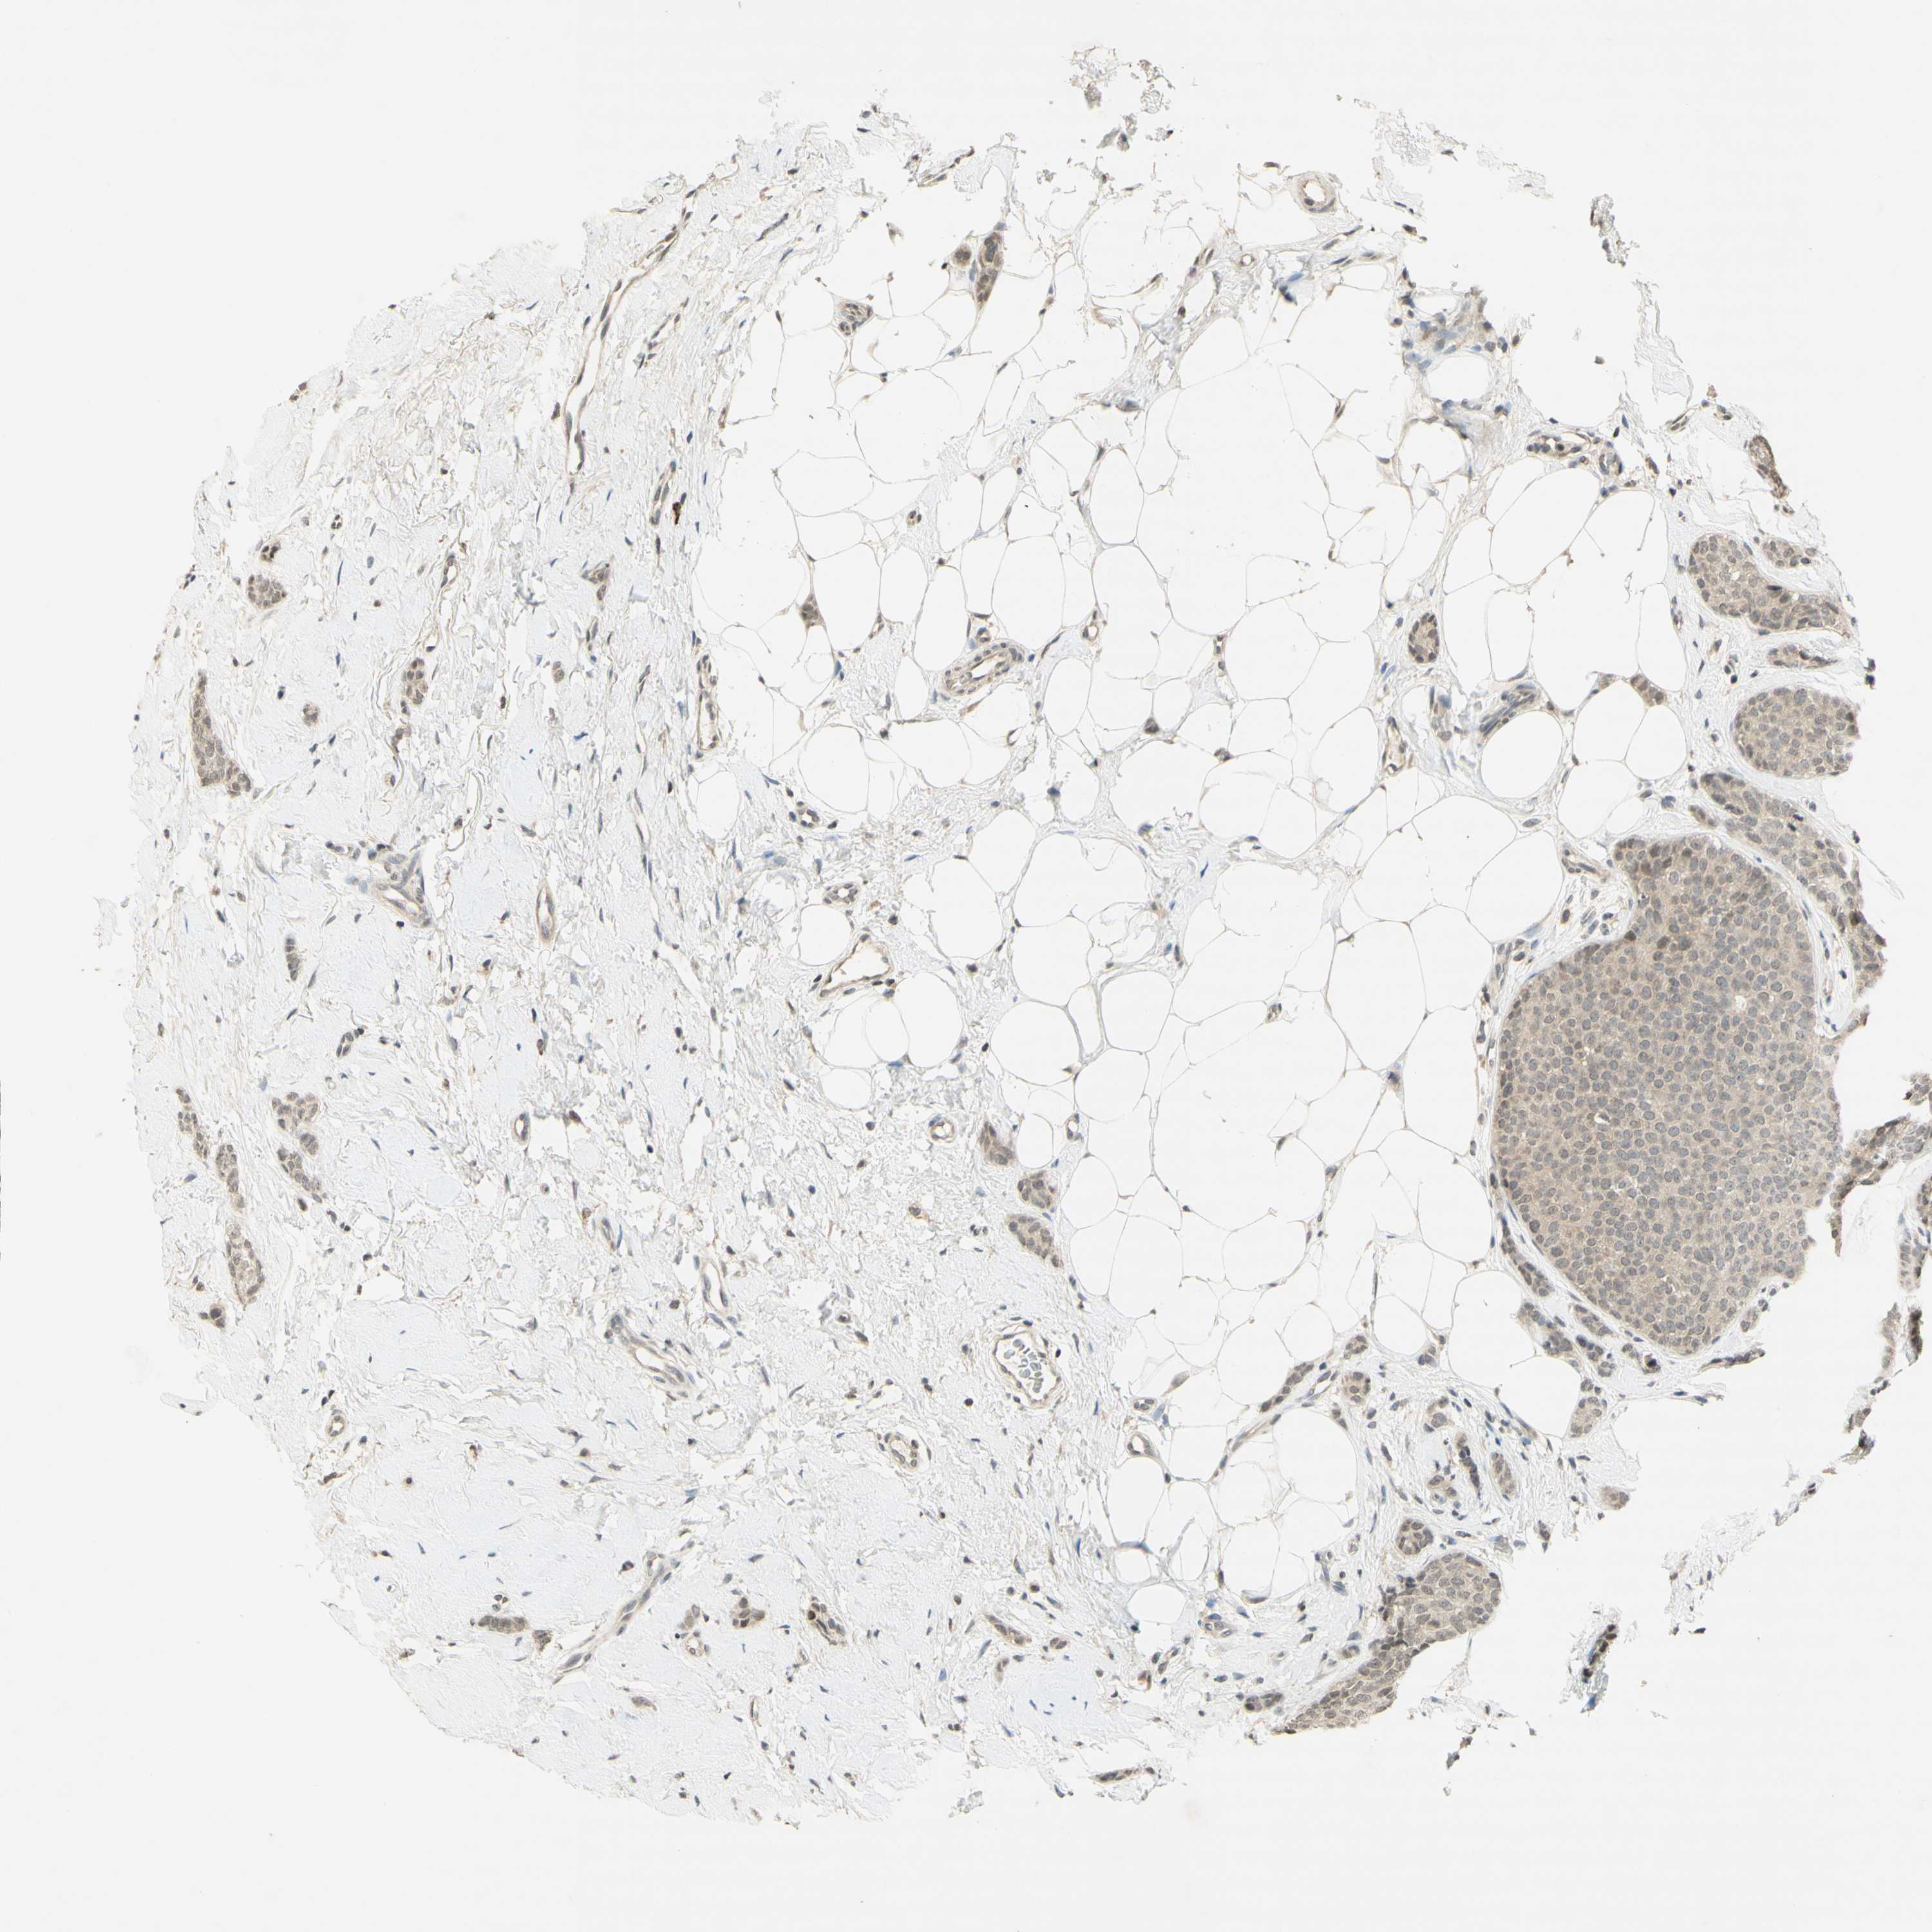

CANCER BREAST CANCER Show tissue menu

BRCA TCGA BRCA VALIDATION PROTEIN EXPRESSION

ANTIBODIES

AND

VALIDATION